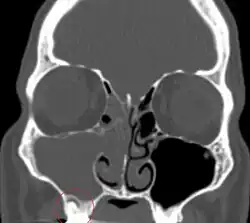

Sinusitis is inflammation of the paranasal air sinuses. Odontogenic sinusitis is an inflammatory condition of the paranasal sinuses that is the result of dental pathology, most often resulting from prior dentoalveolar procedures, infections of maxillary dentition, or maxillary dental trauma.[6] Infections associated with teeth may be responsible for approximately 20% of cases of maxillary sinusitis.[7] The cause of this situation is usually a periapical or periodontal infection of a maxillary posterior tooth, where the inflammatory exudate has eroded through the bone superiorly to drain into the maxillary sinus. Medical management and treatment of the underlying dental pathology remains a critical initial step in the treatment of odontogenic sinusitis, however recent literature suggests that a significant portion of patients may require endoscopic sinus surgery for successful disease resolution.[6] Once an odontogenic infection involves the maxillary sinus, it is possible that it may then spread to the orbit or to the ethmoid sinus.[7]